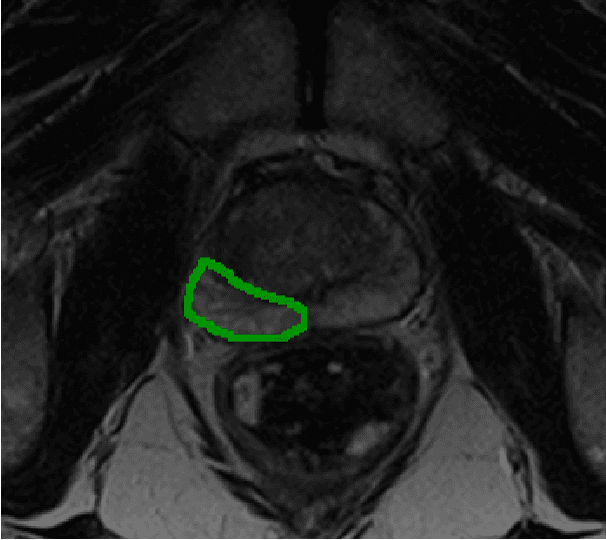

Pilot award

This team is developing AI software that analyses MRI images collected in patients on active surveillance over time to track changes in prostate tumours. The aim is to detect cancer progression early and automatically.

Project leads: Dean Barratt, Geoffrey Sonn

Collaborating institutions: University College London, Canary Center at Stanford (prior partner)